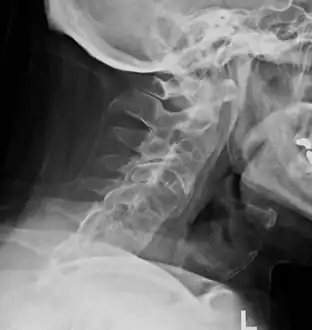

The earliest changes demonstrable by plain x–ray shows erosions and sclerosis in sacroiliac joints. Progression of the erosions leads to widening of the joint space and bony sclerosis. X-ray spine can reveal squaring of vertebrae with bony spur formation called syndesmophyte. This causes the bamboo spine appearance. A drawback of X-ray diagnosis is the signs and symptoms of AS have usually been established as long as 7–10 years prior to X-ray-evident changes occurring on a plain film X-ray, which means a delay of as long as 10 years before adequate therapies can be introduced.[21]

Lateral X-ray of the neck in ankylosing spondylitisImaging -